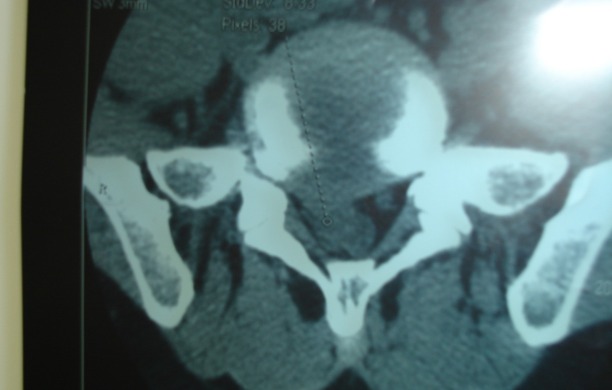

Thessys椎间孔镜优缺点THESSYS可以用于任何疝出的椎间盘微创伤手术。所有隔离的椎间盘物质和腰部脊柱的脱出(包括第5腰椎和第1骶椎间隙)都可以使用整个系统在局麻下经侧方的椎间孔摘除。整个系统的使用适用于任何由疝出的椎间盘或较大的突出引起的神经根症状或长期疼痛,保守治疗不能获得足够的改善。对于任何疝出的椎间盘的手术,THESSYS手术也需要术前彻底的磁共振,计算机断层和常规的放射线影像检查。